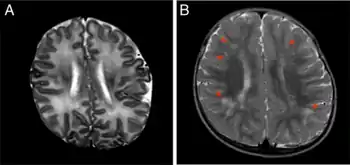

MRI in an infant with congenital cytomegalovirus infection at the age of 1 month and 18 months